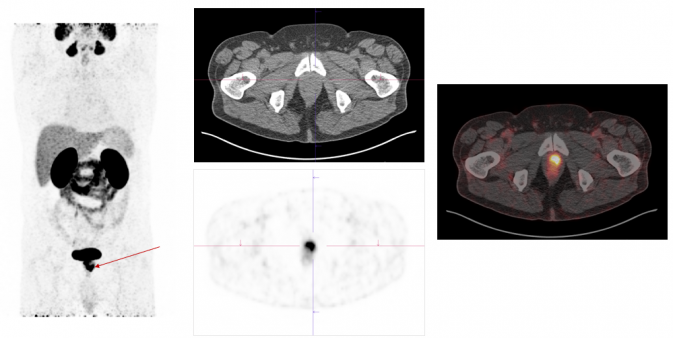

Exemplary case study on PSMA-PET/CT diagnostics: